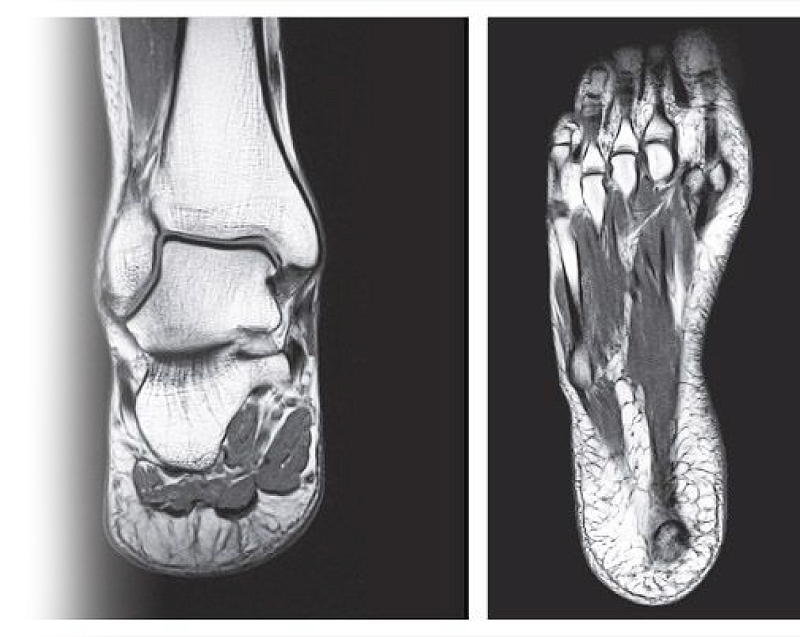

Магнитно-резонансная томография суставов стопы – важный метод исследования, который позволяет визуализировать кости стопы, связки, сухожилия, окружающие мягкие ткани.